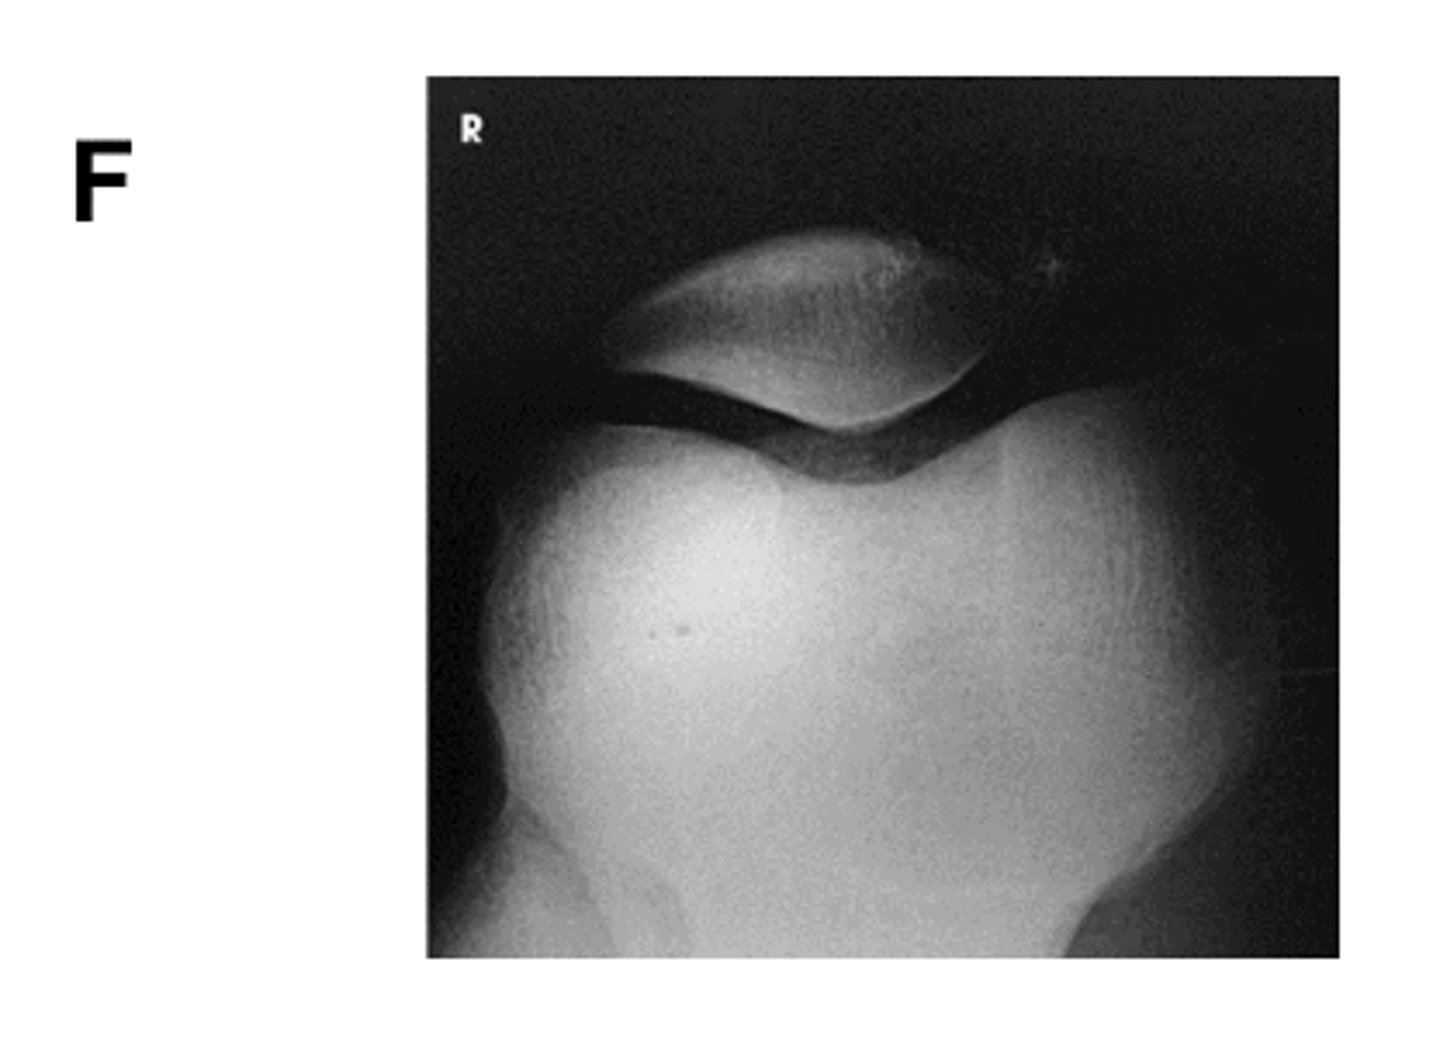

Identify the projection:

Tangential Patella (Settegast Method)

What is the AOI in this projection?

intercondylar fossa